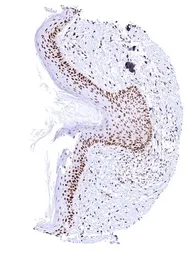

GTX644715 IHC-P Image

IHC-P analysis of human skin tissue using GTX644715 PCNA antibody [HMV4714] HistoMAX™.

In the epidermis, nuclear PCNA staining is most prevalent and intense in basal and suprabasal cell layers and decreases towards the surface.